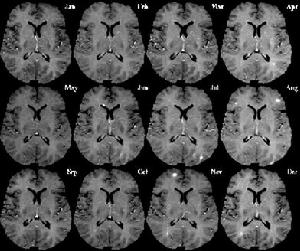

多發性硬化——趨勢圖a、初發症狀常包括一個或多個肢體局部麻木無力、刺痛、發涼,視力下降、視物模糊、復視,平衡障礙,排便功能障礙等多種功能性病變。還有些病人表現急性或漸進性的痙攣性輕截癱和感覺缺失。

(三)MRI( magnetic resonance imaging )

常規MRI檢查對MS的臨床確診患者MRI陽性率>95%。MRI檢查可見大小不一,類似圓形的T1底信號,T2高信號,常見於側腦室前角與后角周圍,半卵圓中心及胼胝體,或為融合斑,多位於側腦室體部;腦幹、小腦和脊髓可見斑點狀不規則T1底信號及T2高信號斑塊;病程長的多數患者可伴腦室系統擴張,腦溝增寬等白質痿縮徵象。多發性硬化引起的震顫